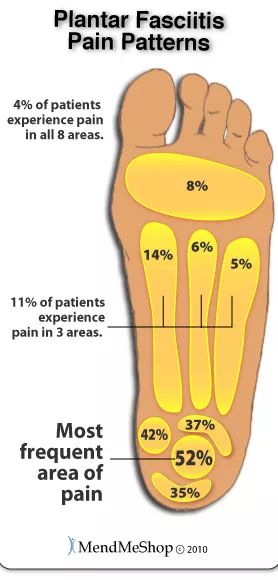

足底筋膜炎通常会引起尖锐的刺痛。

多为单侧。最常见的部位是脚后跟中心地带。左侧的图给出了常见痛点的分布。

疼痛往往发生在早晨刚床时头几步或者休息过后开始走路的时候。当你站起来,多走动一会儿,疼痛通常会减轻,但是长时间站立或行走后,疼痛可能又会卷土重来。